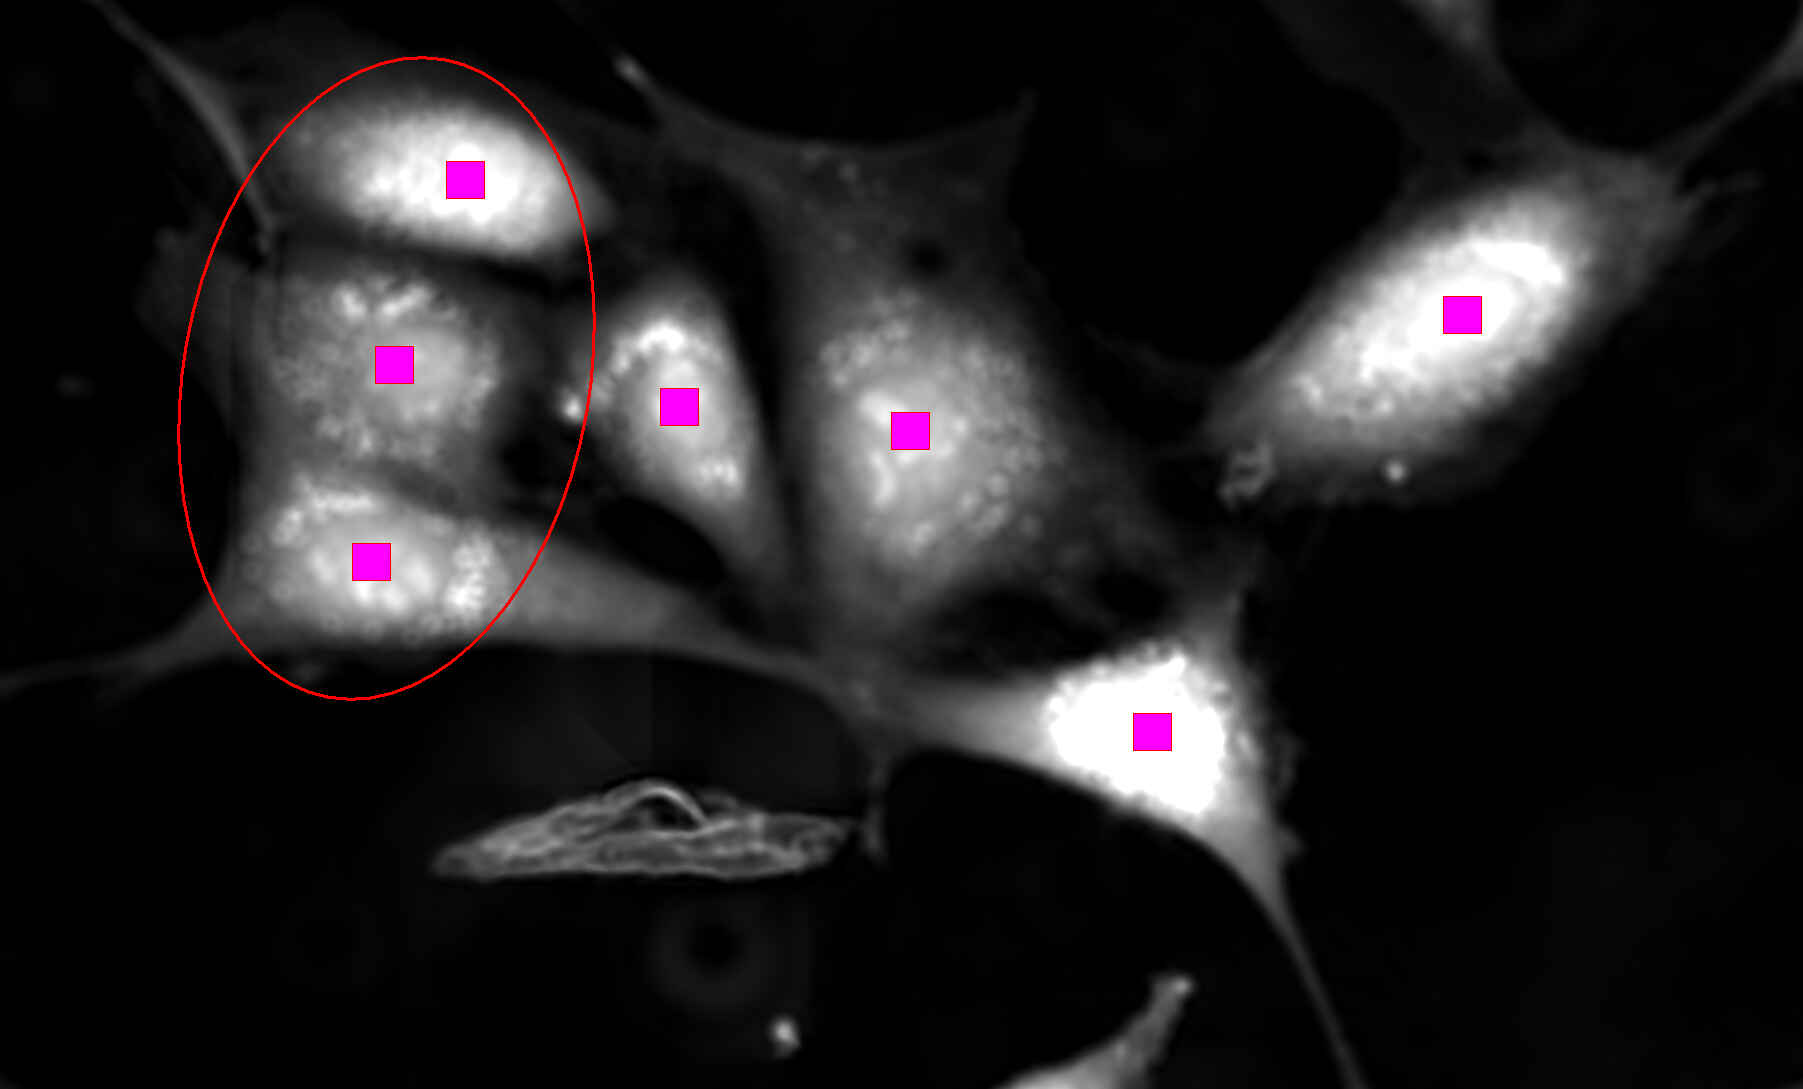

The Ti2-U is a fully manual yet highly stable inverted microscope designed for precision tasks like IVF and micromanipulation. It retains Nikon’s Assist Guide system for status monitoring and alignment help but excludes motorized focus or stage, prioritizing mechanical stability and reliability. With a wide field of view, smooth manual controls, NAMC contrast, and ergonomic layout, the Ti2-U offers excellent clarity and ease of use for labs that need dependable manual performance rather than automation.

Spindle observation (IVF/ICSI model): TI2-C-SO Spindle Observation System

Adjustment Tool: C-T Centering Telescope (for spindle observation)

Compatible objectives (IVF model):

-

CFI Achromat 4X (0.10 / 30 mm)

-

NAMC 10XF (0.25 / 6.20 mm)

-

LWD NAMC 20XF (0.40 / 3.10 mm)

-

LWD NAMC 40XC (0.55 / 2.70–1.70 mm)

-

CFI Plan Fluor 4X (0.13 / 17.20 mm)

-

CFI S Plan Fluor ELWD NAMC 20XC (0.45 / 8.20–6.90 mm)

-

CFI S Plan Fluor ELWD NAMC 40XC (0.60 / 3.60–2.80 mm)